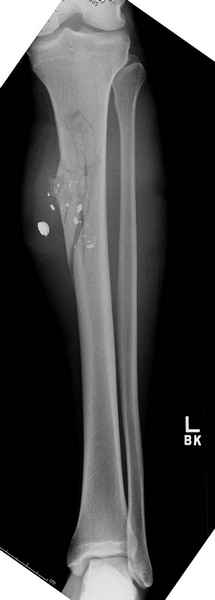

Здесь несколько примеров из нашей практики:

1 неполный перелом большеберцовой кости перкутанная пластина